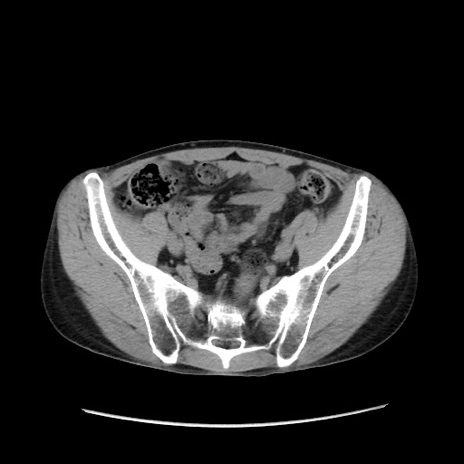

症例37(横断像)

【症例】40歳代 男性

【主訴】腹痛

【現病歴】4時間ほど前に電車に乗車中に臍部上より腹痛出現。徐々に増悪し起立困難となり、救急外来受診。生ものは数日食べていない。今朝お雑煮を食べた。

【身体所見】BT 36.8℃、BP 117/84mmHg、HR 91/min、SpO2 97%、苦悶様、腹部:臍上部広範囲圧痛あり、反跳痛±

【データ】WBC 8100、CRP 0.03